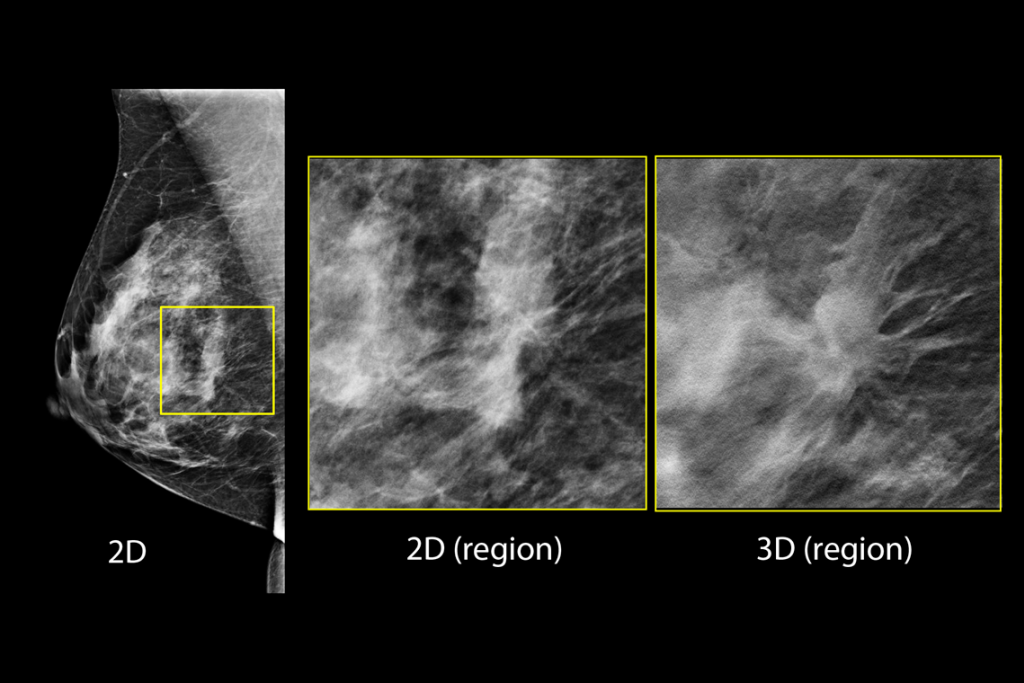

Klinische Aufnahmen einer Brustuntersuchung